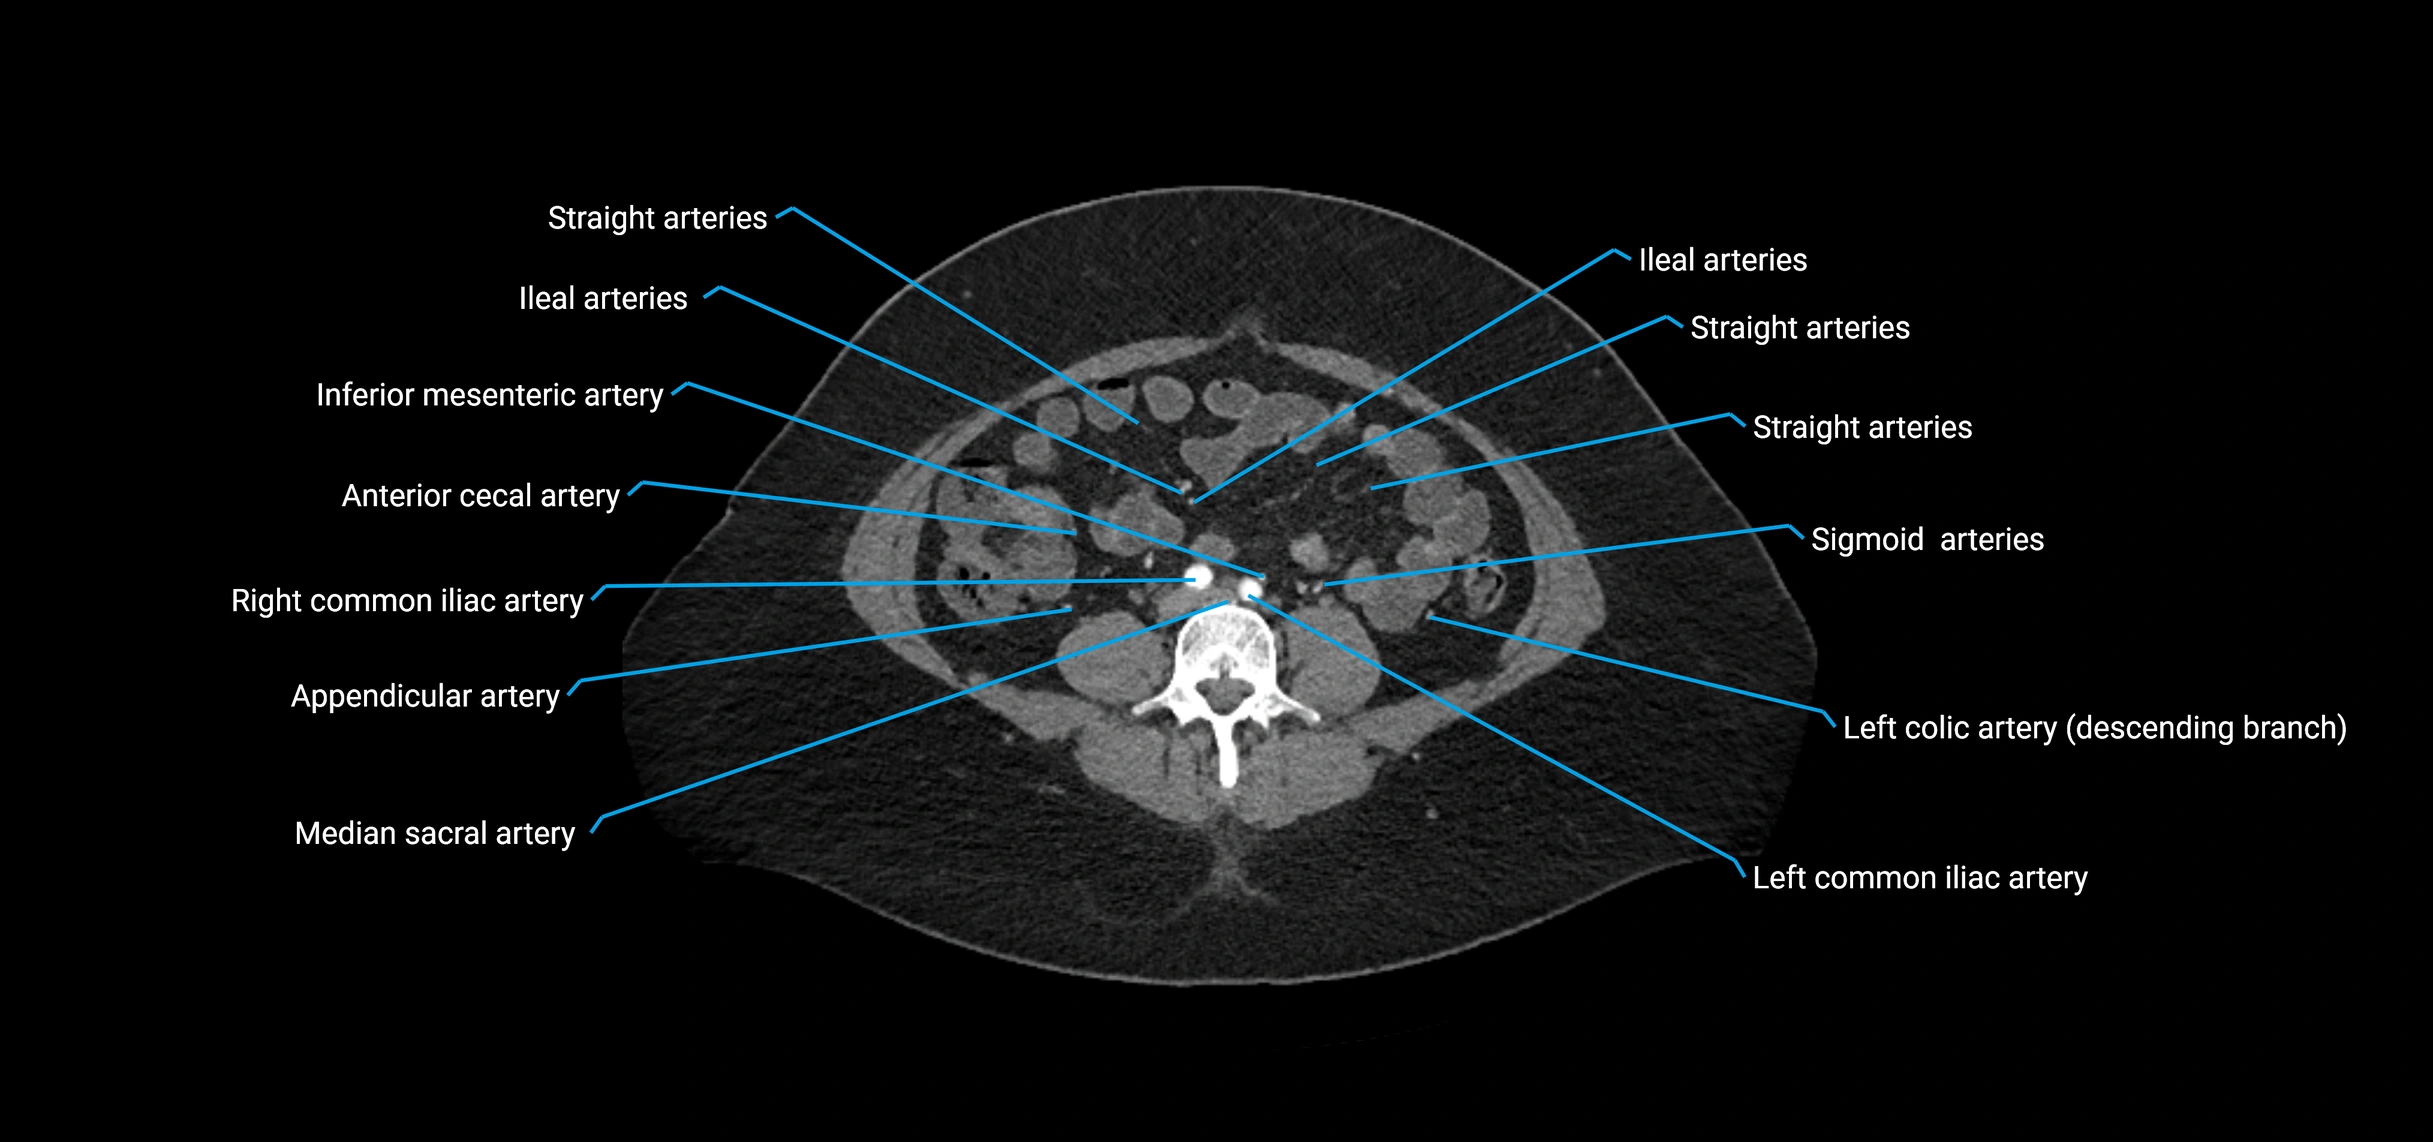

CT images

image

Contrast-enhanced CT (CTA):

• Gold standard for abdominal aortic imaging

• Provides excellent detail of lumen, wall, aneurysm, thrombus, and branch vessels

• Multiplanar and 3D reconstructions help in aneurysm measurement, stent graft planning, and dissection evaluation